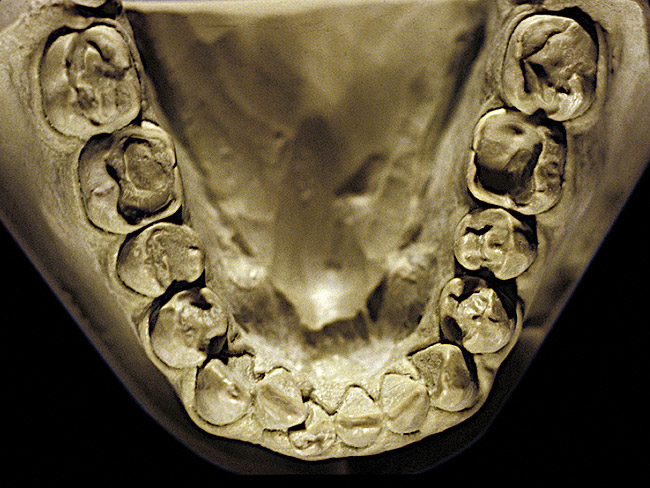

Figure 24 and Figure 25 exhibit NCLTS from fruit-mulling. The posterior teeth were affected to a greater extent than the anterior teeth, with the maxillary and mandibular posterior teeth affected equally, not only to each arch, but every tooth juxtaposed to each other. Cupping and cratering was present with abraded enamel edges from the mulling action. The diagnosis was confirmed from the pathognomonic pattern along with the match-up of abraded enamel edges peripheral to the cups and craters and the admission of the habit by the patient.

Figure 24  Moderate NCLTS from fruit-mulling, maxillary arch.

Figure 24

Figure 25  Moderate NCLTS from fruit-mulling, mandibular arch.

Figure 25